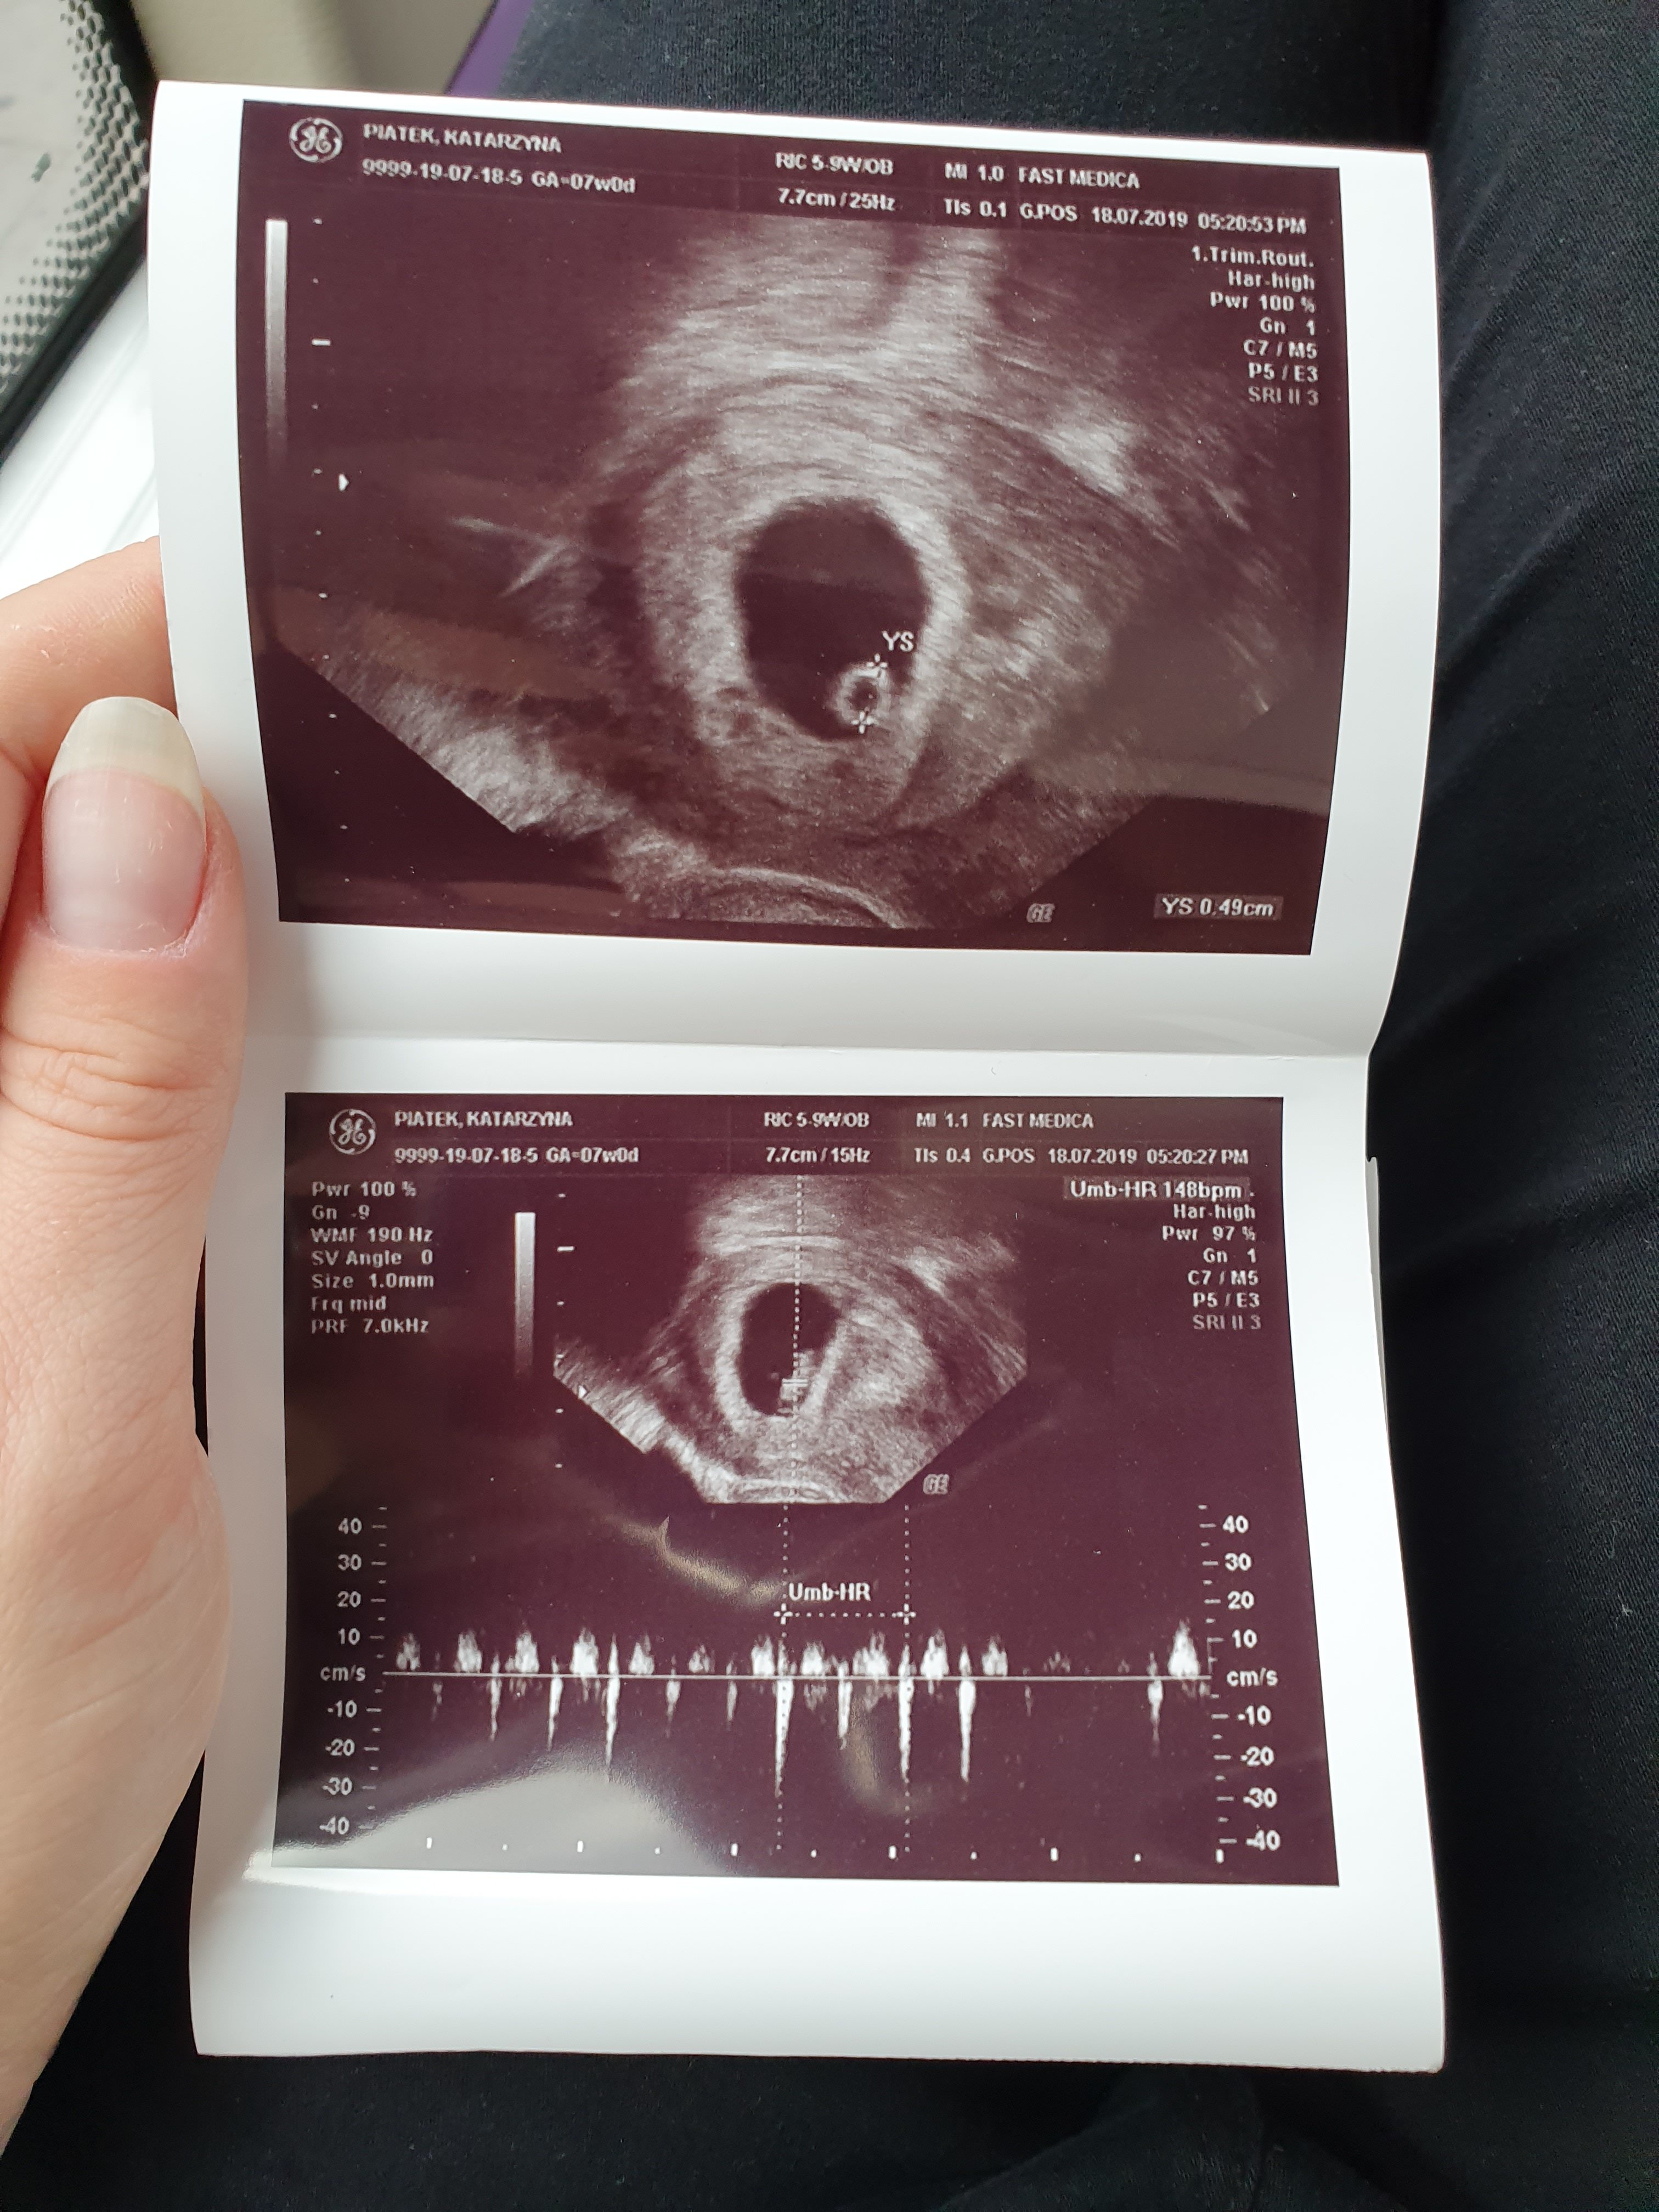

Hej dziewczyny ja byłam wczoraj na wizycie.

Nie miałam plamien ani razu ale dostałam progesteron na miesiąc oraz zakaz seksu

Powiedział że jest krwiak który jakby miał zrobić coś groźnego to już by zrobił ale.lepiej niech się szybko wsiaknie.

Ciaza rozwija się prawidłowo serduszko bije prawidłowo

Wiek ciazy 7t2d

Termin na 3.03

Cieszę się bardzo ❤